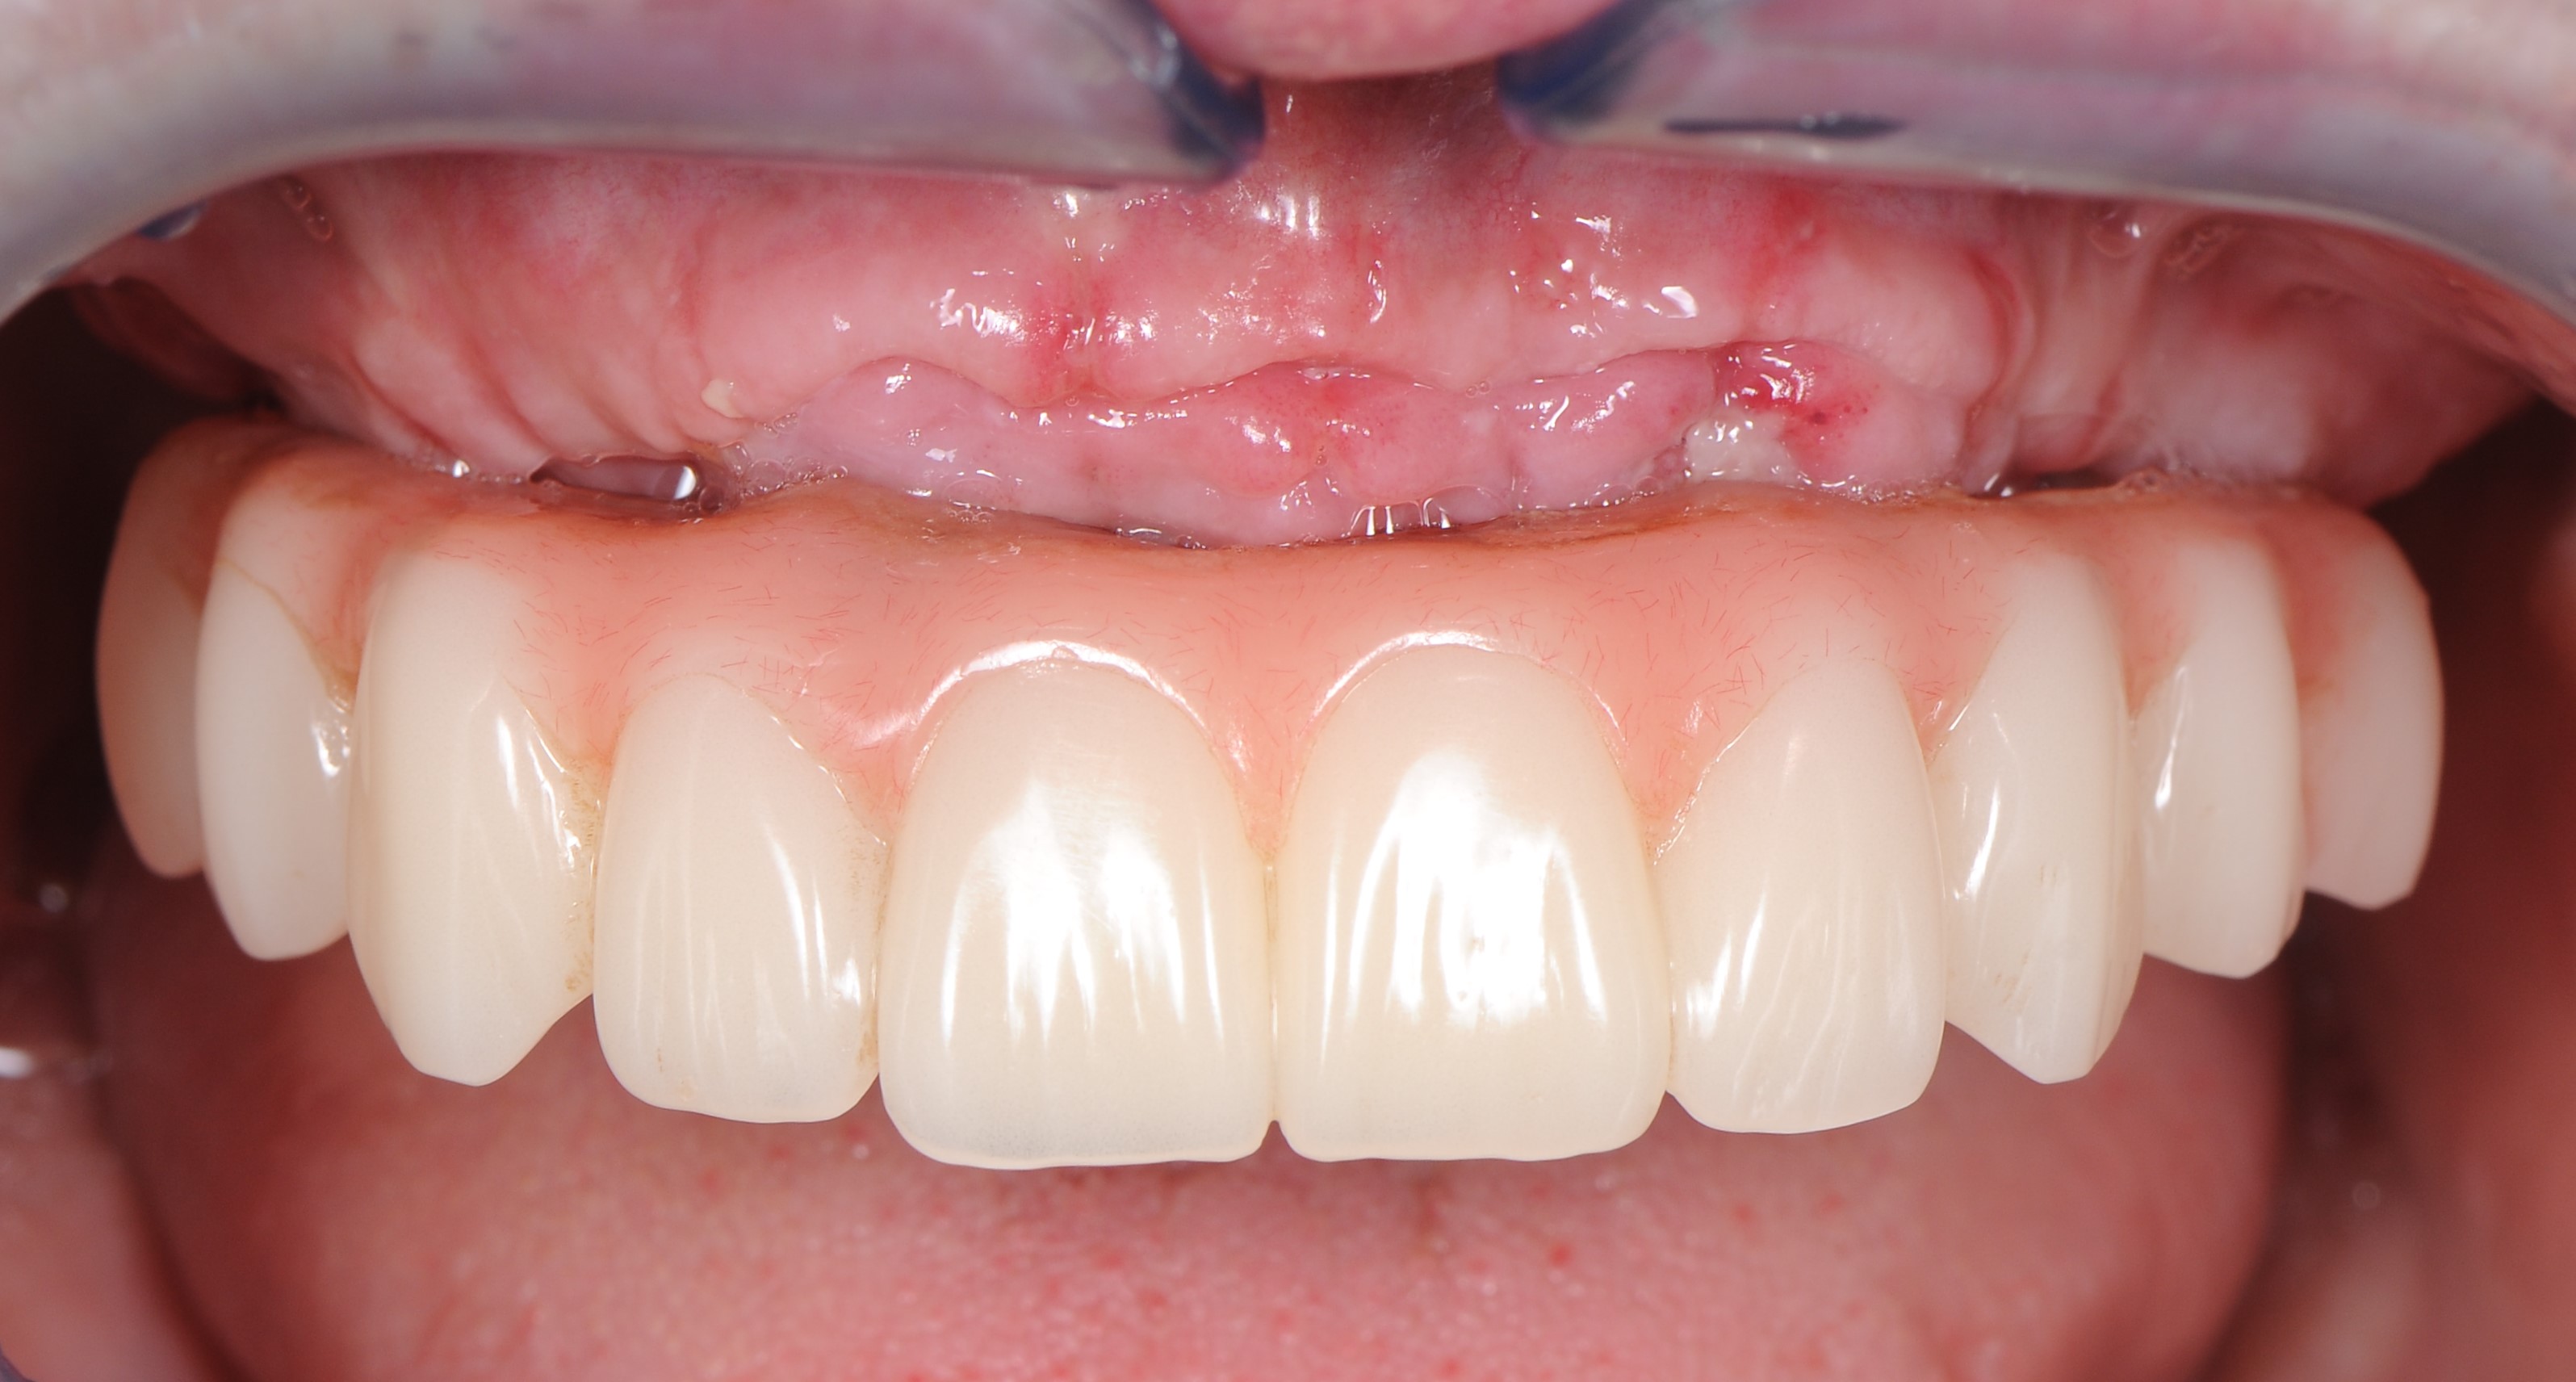

Через 6 месяцев на этапе постоянного протезирования сняли временный протез с имплантатов верхней челюсти и провели контрольную рентгенографию для контроля качества остеоинтеграции каждого из имплантатов. Также оценивали состояние мягких тканей окружающих «Multi – unit» абатментов (рис. 40,41)

Через 8 месяцев после имплантации была зафиксирована несъёмная мостовидная керамическая конструкция с титановым каркасом по методике «All – on – 4» (рис. 46).